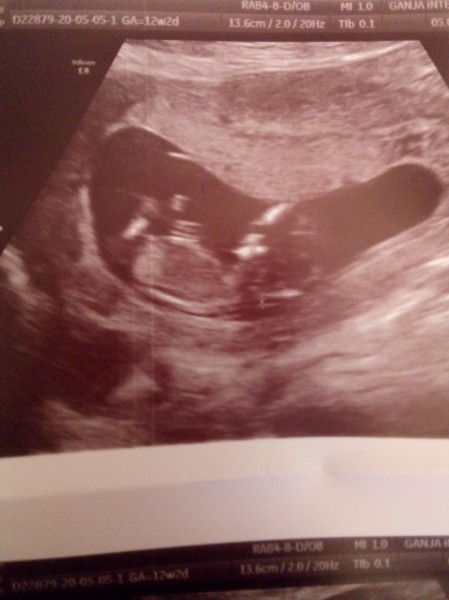

İyi aksamlar hanimlar, buda benim minik muzicem dr geldik ense kalinligi 1.5 dedi ama 3 gun sonraya tekrar randevu verdiler sorun yok dedi ama anlamadım neden tekrar bakmak istedi, bide hep elleriyle yuzunu kapatdi burnunu tam goremedi.

Gebelik haftası 12+2